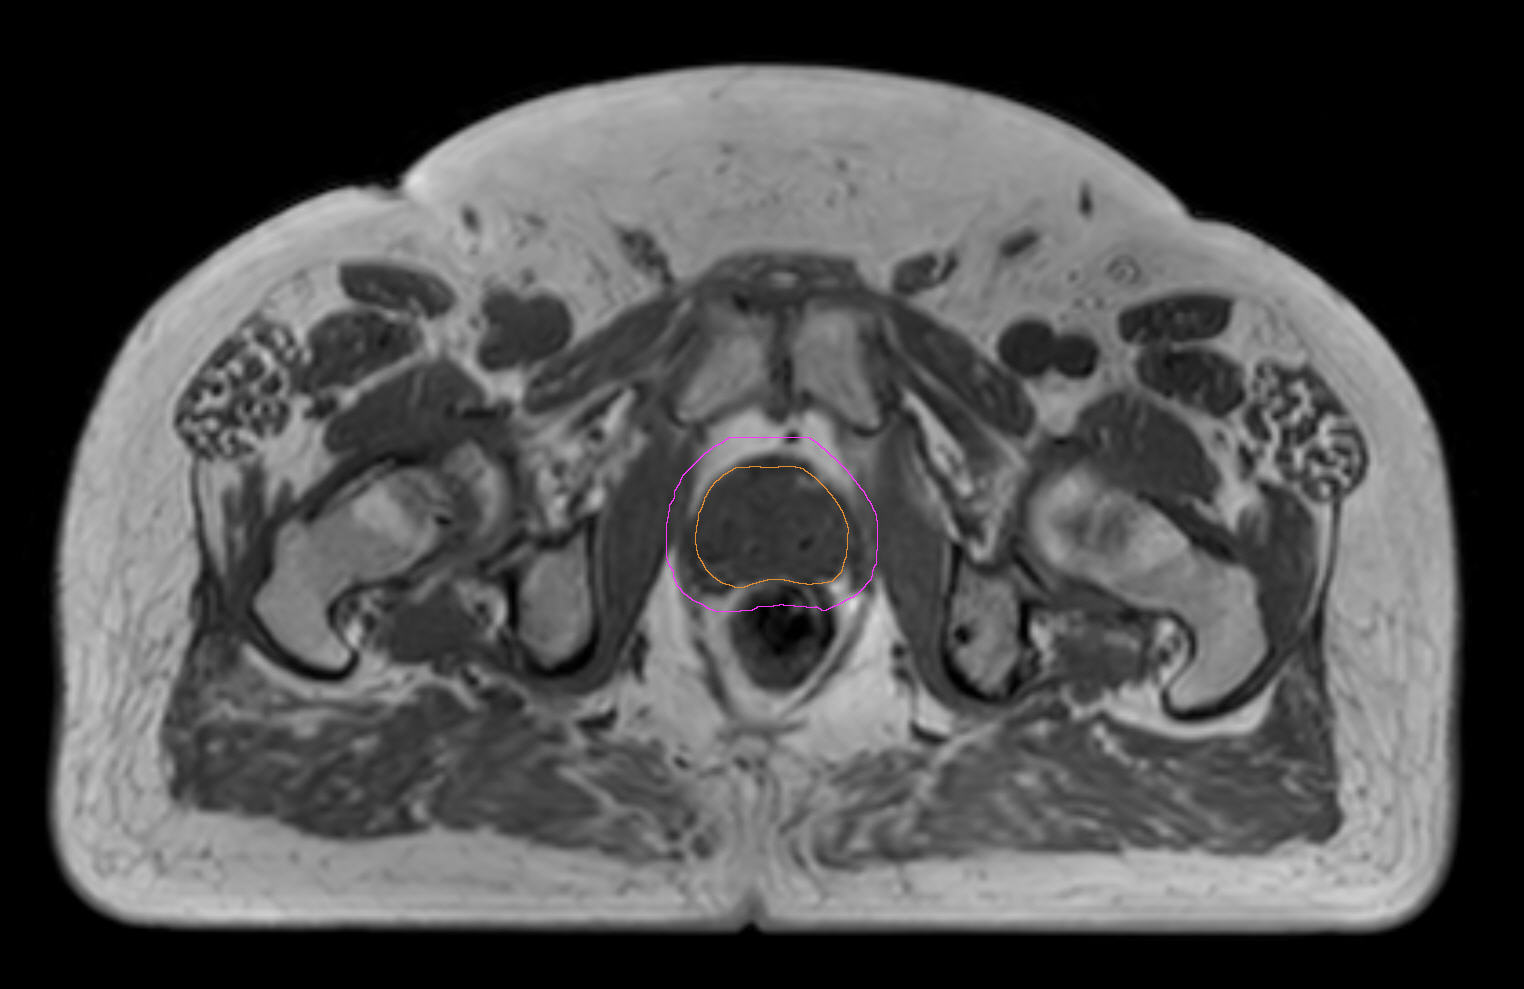

77-year-old male with prostate cancer cT3aN0M0, Gleason 8 and PSA 52 µg/L referred to androgen deprivation and radiation therapy with a prescribed dose of 50 Gy to the pelvic lymph node regions and 76 Gy to the prostate. Patient underwent MRI on Ingenia MR-RT 1.5T using FlexCoverage Anterior Coil in combination with the integrated Posterior Coil. Dose planning was performed on MRI imaging data.